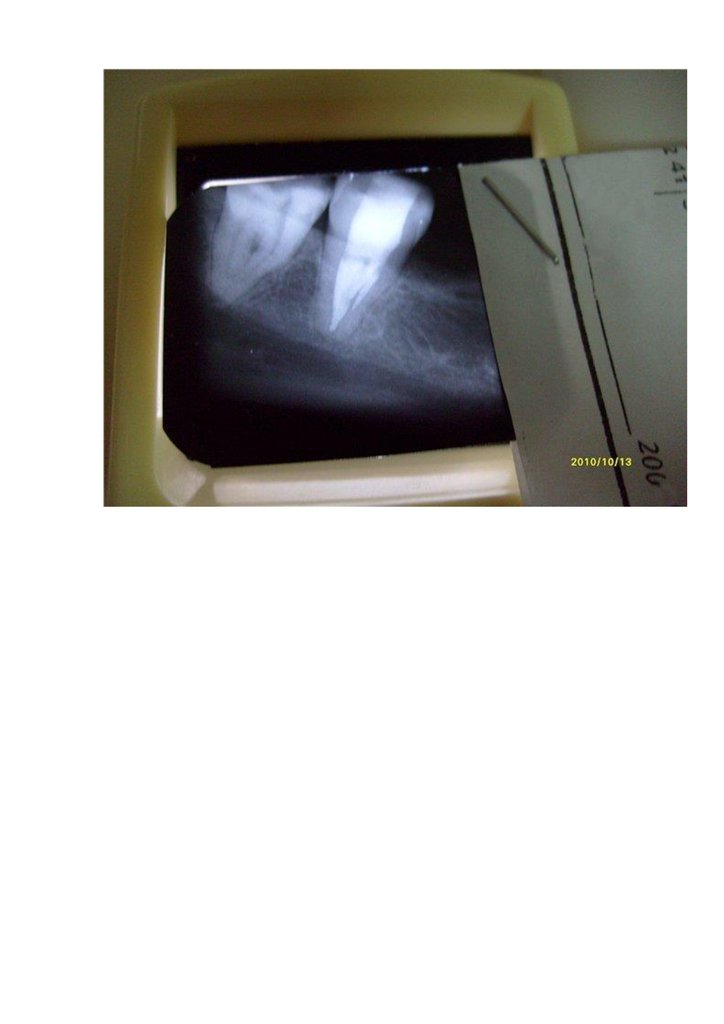

В нижних 4 и 5 зубах примерно как в нижних резцах, на рисунке (он вообще-то 45,

но в зеркале отражается как 35) начинать препаровку в отмеченной точке,

направляя мысленно кончик бора к середине зуба на уровне десны.

Еще 35

Это 34